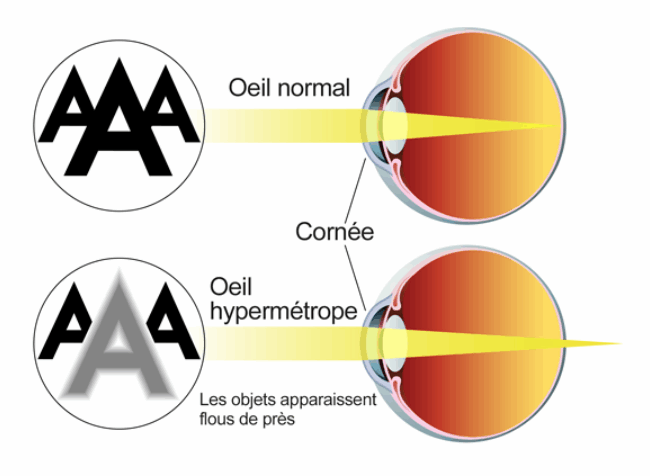

Les principaux défauts de la vision:

- Chez un individu hypermétrope, la vision est nette de loin et flou de près.Ici l'oeil est trop court et/ou la cornée trop plate. Par conséquent, l’image se forme en arrière de votre rétine.